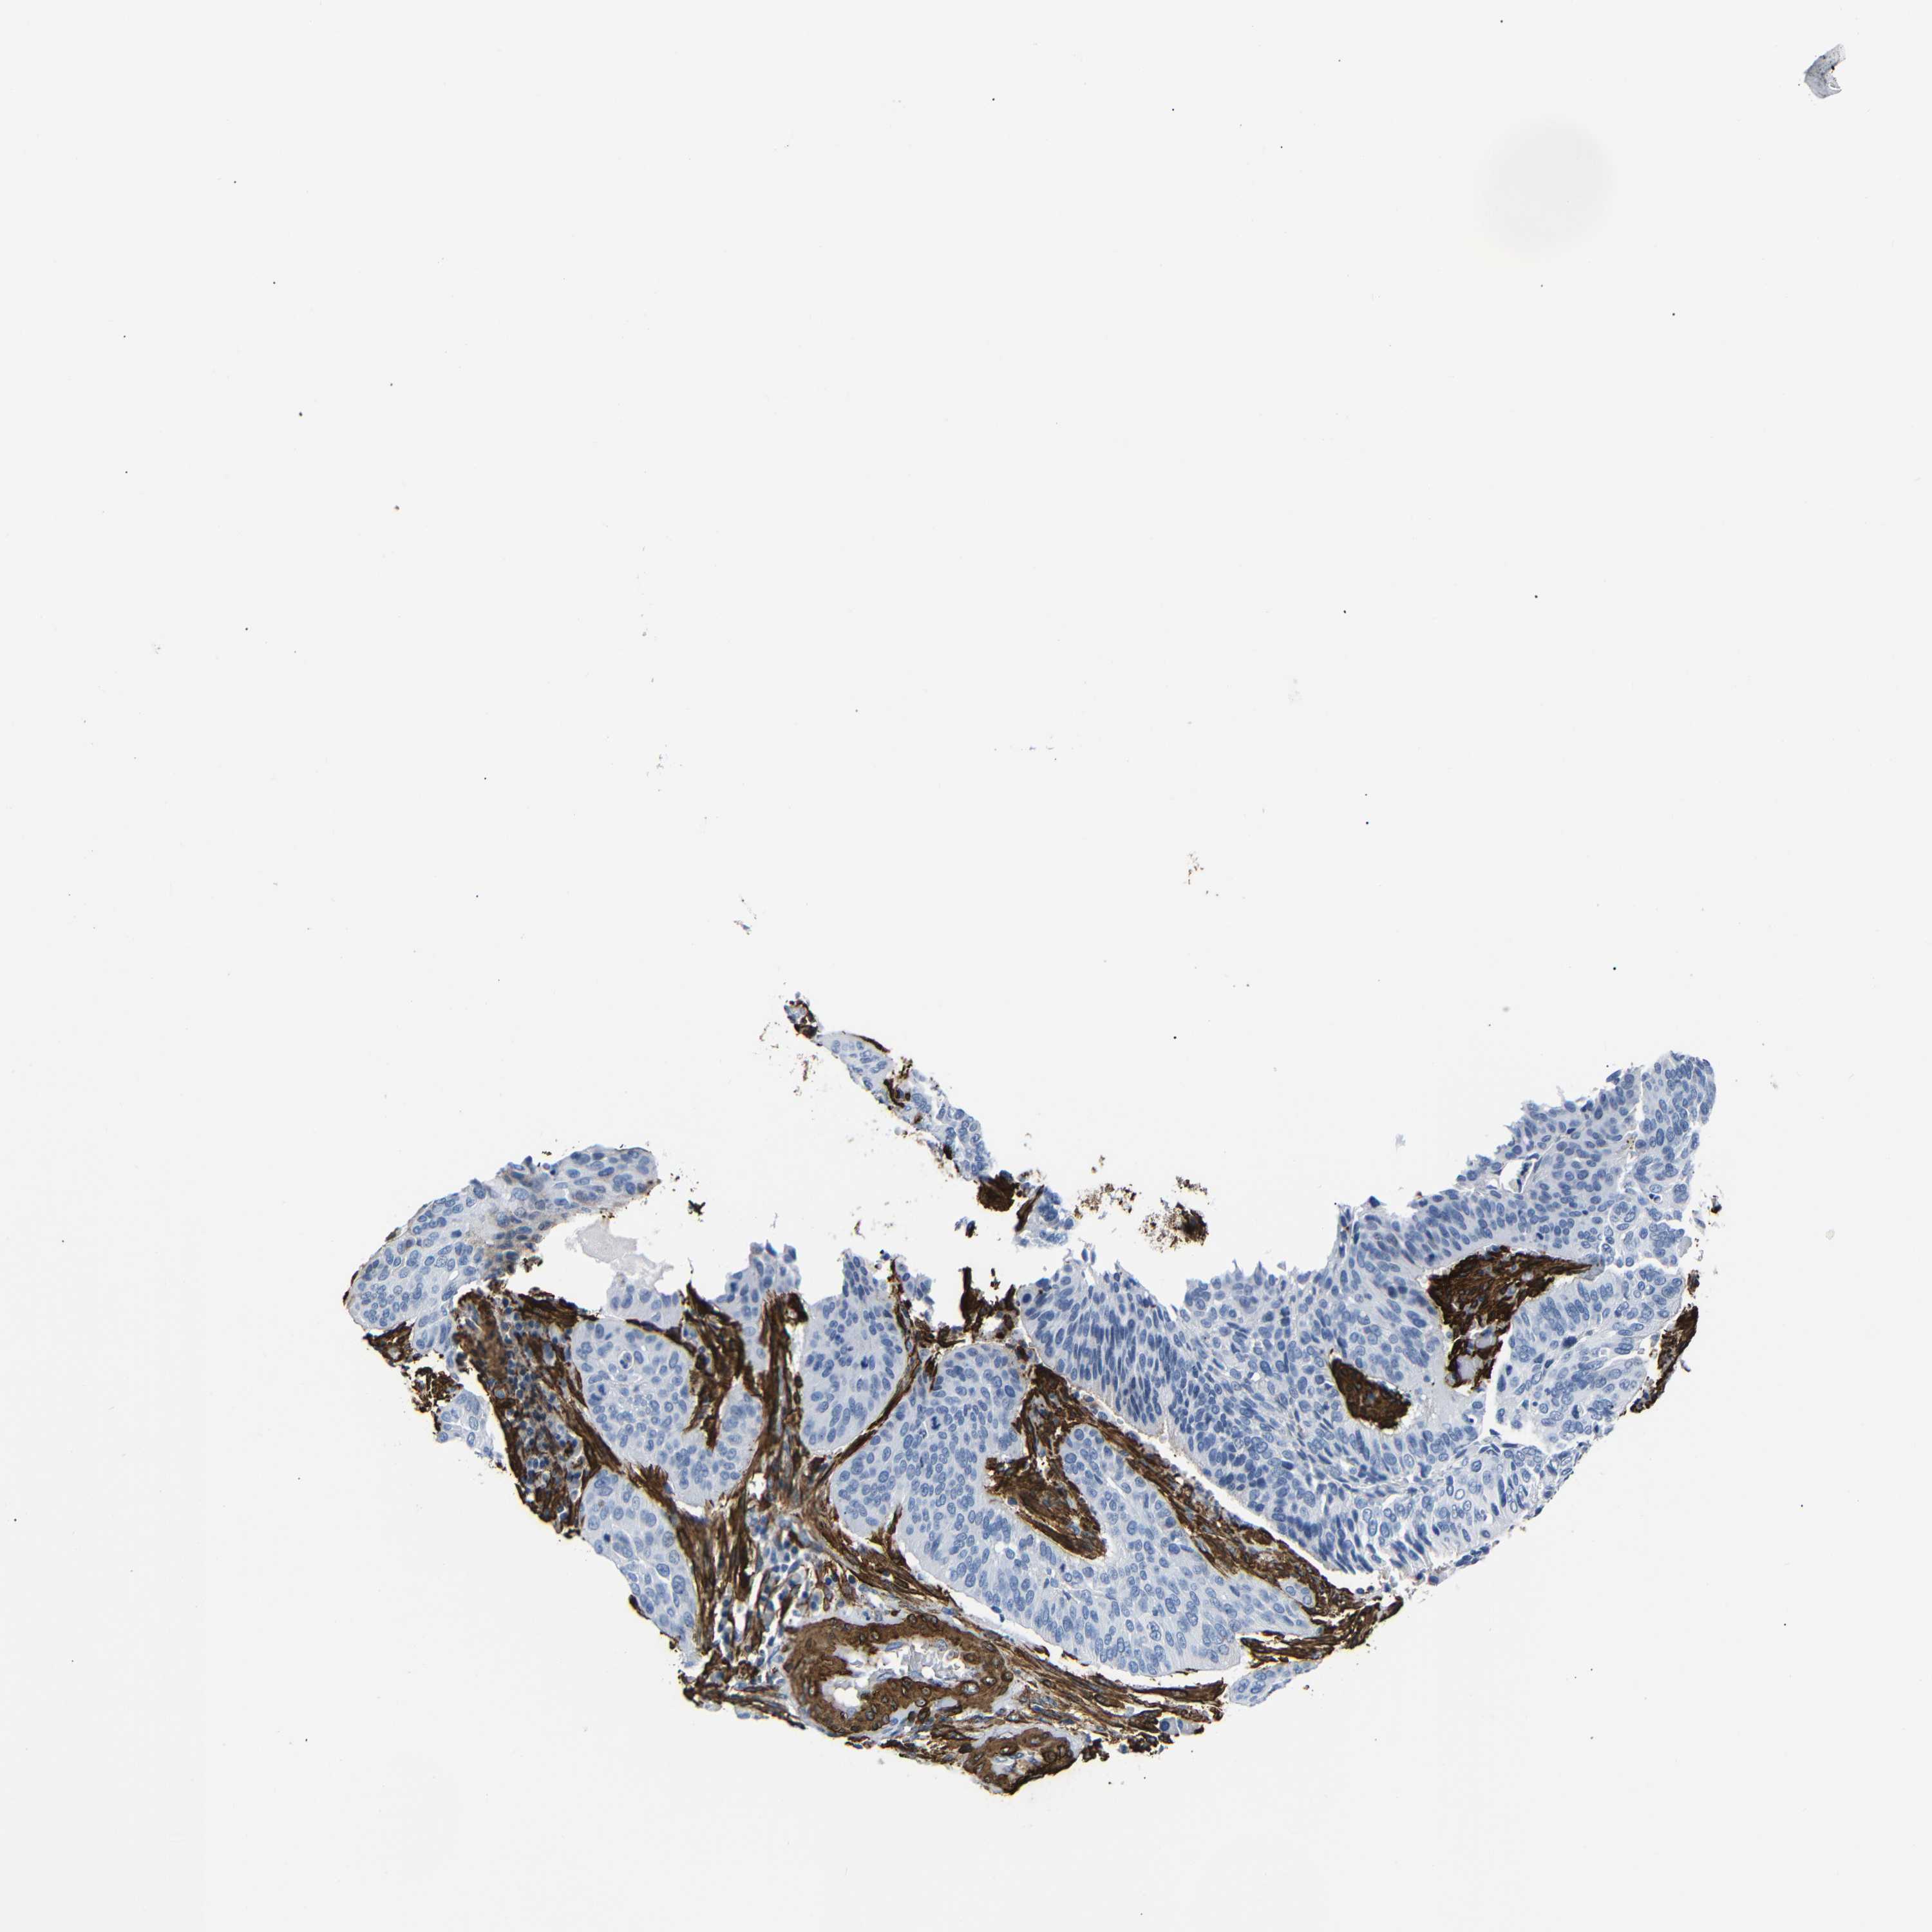

CERVICAL CANCER - Protein expressioni

A mouse-over function shows sample information and annotation data. Click on an image to view it in a full screen mode. Samples can be filtered based on level of antibody staining by selecting one or several of the following categories: high, medium, low and not detected. The assay and annotation is described here.

Note that samples used for immunohistochemistry by the Human Protein Atlas do not correspond to samples in the TCGA dataset.

Antibody stainingi

Antibody staining in the annotated cell types in the current human tissue is reported as not detected, low, medium, or high, based on conventional immunohistochemistry profiling in selected tissues. This score is based on the combination of the staining intensity and fraction of stained cells.

Each image is clickable and will lead to virtual microscopy that enables deeper exploration of all samples and also displays staining intensity scores, fraction scores and subcellular localization as well as patient and tissue information for each sample.

HPA041264

HPA041271

CAB000002

CAB003761

CAB013531

Staining

High

Medium

Low

Not detected

Intensity

Strong

Moderate

Weak

Negative

Quantity

>75%

75%-25%

<25%

None

Location

Nuclear

Cytoplasmic/membranous

Cytoplasmic/membranous,nuclear

Squamous cell carcinoma, NOS

Adenocarcinoma, NOS